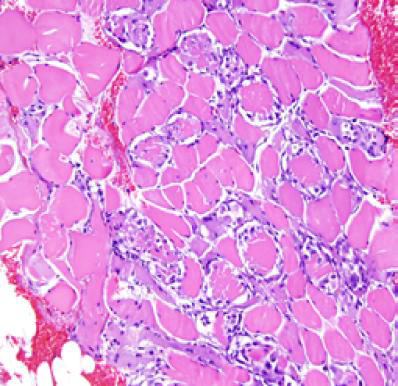

Haff disease is defined as unexplained rhabdomyolysis following ingestion of some sea fish and crayfish. First reported in 1926 from the Baltic region, its pathophysiologic mechanism is largely unknown, but toxins release have been implicated. Common features include generalized myalgia, brown/ dark urine, elevated serum creatine kinase and creatinine, kidney dysfunction can be severe enough to cause acute kidney injury (AKI). We present the case of a 28-year-old man who ate cooked freshwater fish and initially presented with diffuse myalgia, headache and brown-colored urine, and later fever and diarrhea. He had severely elevated serum creatine kinase and creatinine, and was managed as a case of Haff disease related AKI (HDRAKI) complicated by sepsis. He had haemodialysis and antibiotics, and recovered kidney function. A detailed history of recent diet and occupational exposure is essential in the diagnosis and management of HDR-AKI. Dialysis could be life-saving.